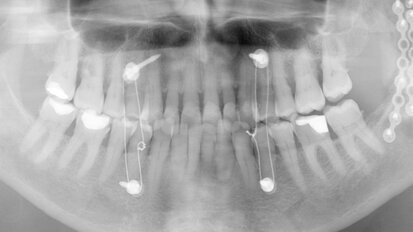

Anterior crowns on teeth and an implant

Dental technicians have so many different restorative materials and design and finishing concepts available to them that it can seem difficult to select the...